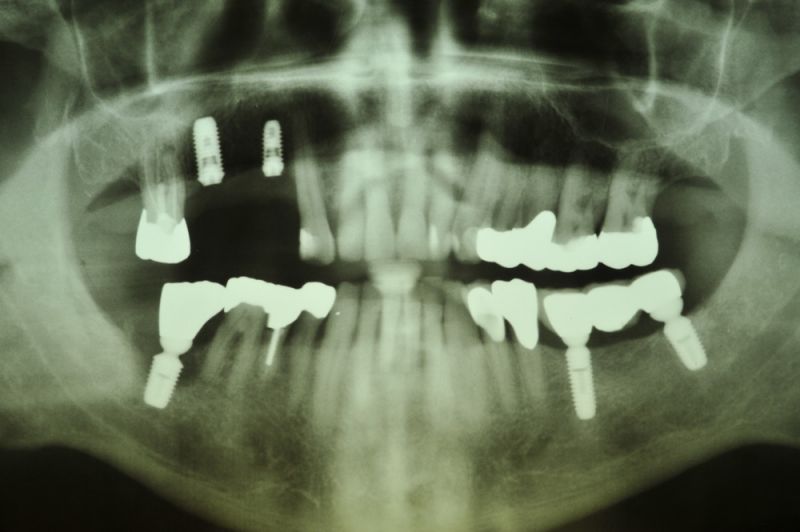

Vor ca. 20 Jahren wurde der Patient umfassend funktionstherapeutisch versorgt. Bereits zum damaligen Zeitpunkt waren die Zähne des Patienten vorgeschädigt und es lag eine Parodontalerkrankung vor.

In der Zwischenzeit sind vorgeschädigte Zähne verloren gegangen und wurden zum Teil durch Implantate ersetzt.

Über eine mehrjährige Phase wurden immer wieder Laborgefertigte Dauerprovisorien eingegliedert, weil vor einer abschließenden funktionstherapeutioschen Behandlung erst noch andere Problemzonen beseitigt werden mussten.